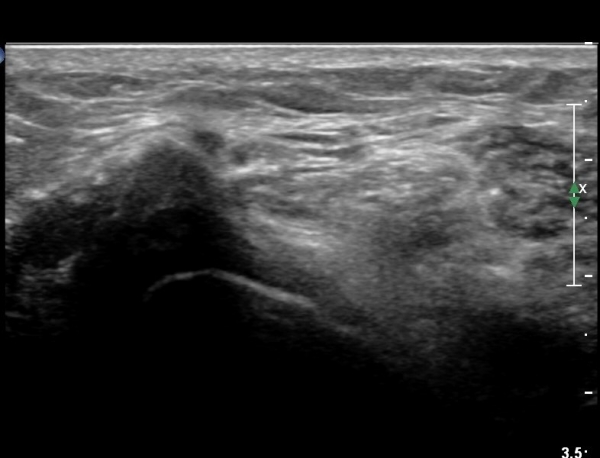

ŽÃËÀÚ¸¦ Á» ´õ ¸»´Ü, ¿ÜÃøÀ¸·Î À̵¿ÇÏ´Ï ºñ°ñµÎ Ç¥Ãþ¿¡¼­ ºñ°ñ½Å°æÀÌ Àú¿¡ÄÚ·Î °üÂûµÈ´Ù(»çÁø 3, 4, 5).